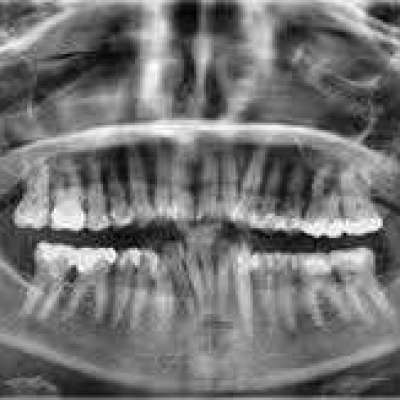

Carestream Dental India Pvt Ltd provides advanced Dental OPG systems for comprehensive panoramic imaging. Designed for clarity and accuracy, our solutions support precise diagnostics and effective treatment planning for dental professionals across India.